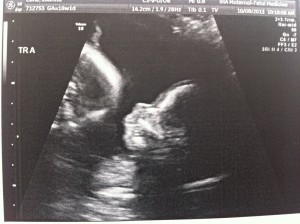

Hello! I had my bi-weekly ultrasound today and, if a triplet pregnancy appointment could be uneventful, this one was it!

Everything still looks great. The triplets are growing but we won’t have another growth scan until my 22wk appointment. Heart beats look good and it’s clear they’re getting bigger (Today’s pictures attached.)